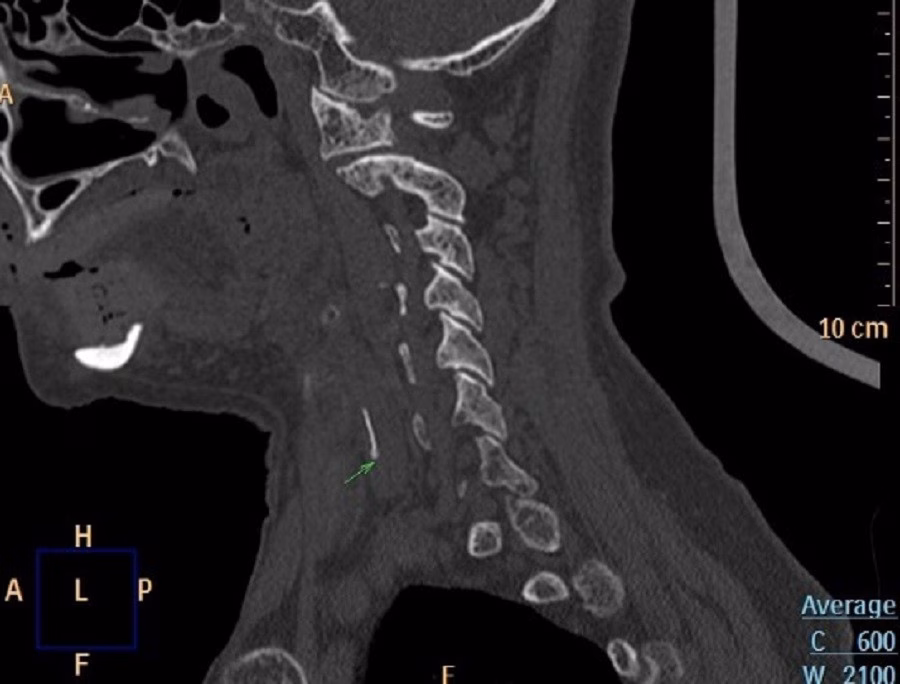

Sau khi được đưa đến phòng khám, nội soi Tai Mũi Họng phát hiện phù nề nghiêm trọng ở vùng sụn phễu trái. X‑quang cổ nghi ngờ có dị vật và CT xác định một mảnh xương cá kích thước khoảng 1×22 mm đã xuyên ra khỏi ống tiêu hoá, cắm sâu vào thùy trái tuyến giáp.